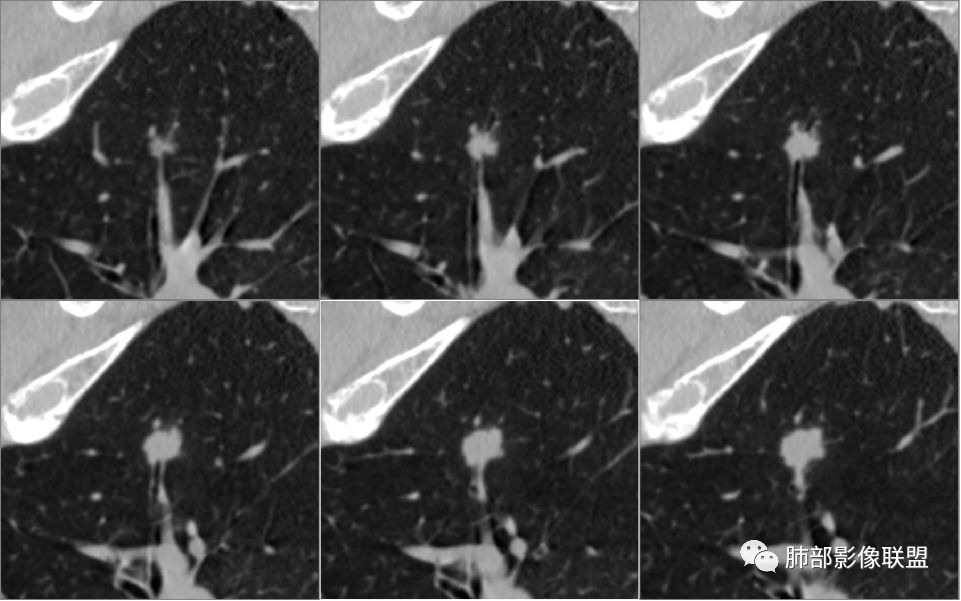

病例1为胸膜下实性小结节,血管脐凹样出入,可见支气管阻塞。病灶膨隆,部分边缘平直,周围晕征不明显,未见分叶,但可见毛刺及胸膜牵拉,增强后明显强化,老年男性,怀疑新生物尤其是腺癌是有理由的。